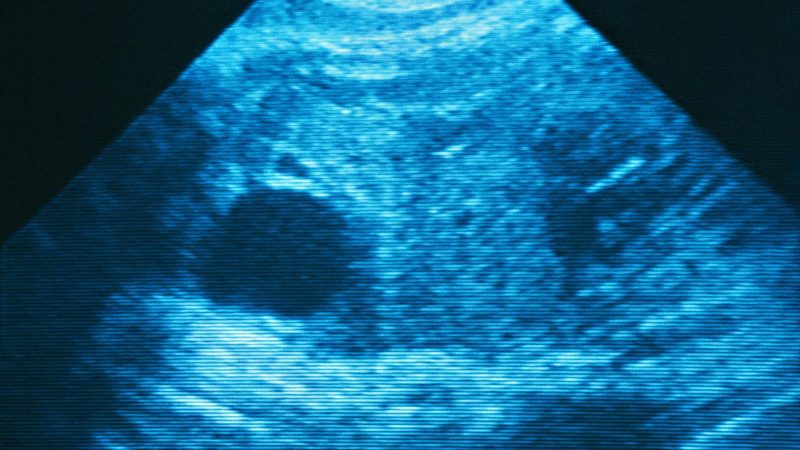

Women suffering from chronic diseases or any severe condition should consult an obstetrician & gynecologist before conceiving or anywhere before planning a baby in future. This will help in cutting down the risks of complications during pregnancy. In case the woman has already conceived the baby, proper screenings, timely tests and ultrasounds may reduce the risk of complications to a large extent.